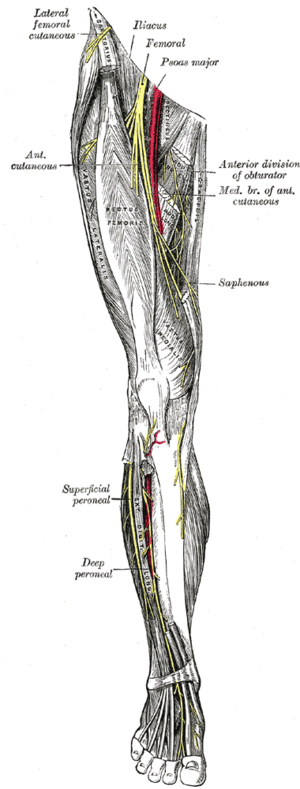

Obturator nerve entrapment

Clinical Features

- Pain in groin and down inner thigh

- Aggravated by movement of the hip